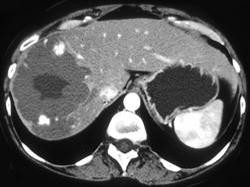

男,46岁,右上腹胀痛不适2月余,请结合CT图像,选择最可能诊断 ( )A、肝囊肿B、肝转移癌C、肝血管瘤D、肝脓肿E、肝癌

问题 男,46岁,右上腹胀痛不适2月余,请结合CT图像,选择最可能诊断 ( )

选项 A、肝囊肿 B、肝转移癌 C、肝血管瘤 D、肝脓肿 E、肝癌

答案 C